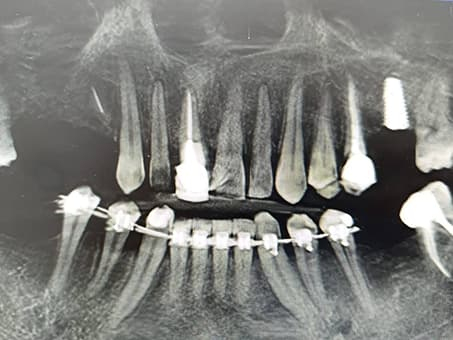

- Установка имплантатов;

Так же, минимальные повреждения костной ткани на месте удаления позволяют в будущем без проблем установить имплантаты.